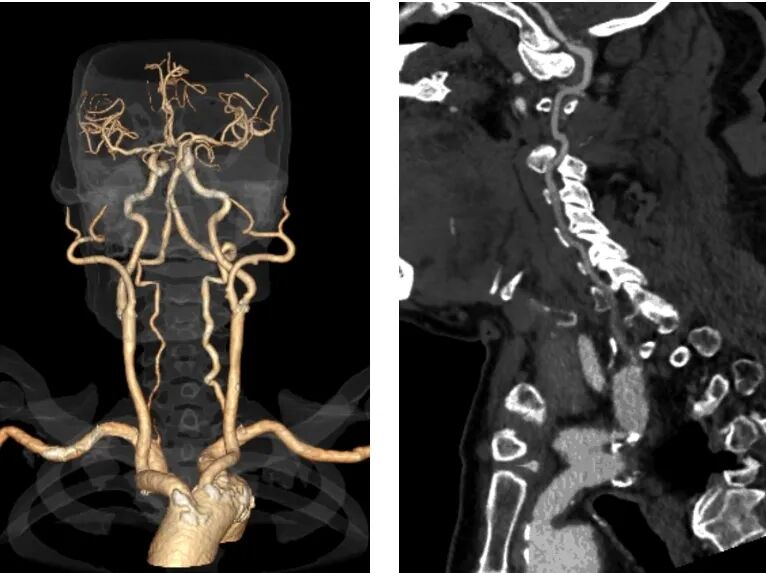

病例一

· 病例介绍

▪男,76岁。

▪“腰背部手术”50余年,长久平卧腰痛。

▪本次CTA发现右侧锁骨下动脉起始部狭窄伴盗血。

· 左侧桡动脉入路造影

明确右侧锁骨下动脉起始部重度狭窄及盗血